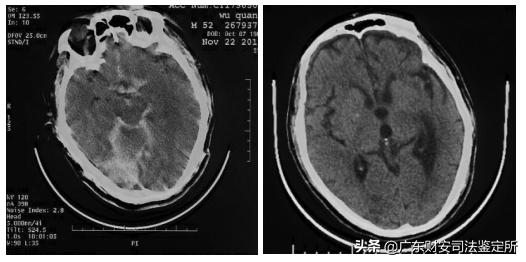

2016年11月22日及11月29日CT片:脑室系统、脑池、小脑幕、双侧大脑半球脑沟回表面见广泛条带状致密影,中脑左侧团片状致密影,左侧额叶见小片状致密影,复查显示脑室、脑池及脑回表面病变较前略吸收。提示脑室积血,广泛蛛网膜下腔出血,中脑左侧份血肿,左侧额叶挫裂伤。

复阅被鉴定人受伤当时及之后复查CT片示脑室系统、脑池、小脑幕、双侧大脑半球脑沟回表面广泛条带状致密影,中脑左侧团片状致密影,左侧额叶小片状致密影,复查显示脑室、脑池及脑回表面病变较前略吸收,提示脑室积血,广泛蛛网膜下腔出血,中脑左侧份血肿,左侧额叶挫裂伤。其脑室积血、广泛蛛网膜下腔出血、中脑左侧份血肿等影像学征象符合左侧颈内动脉瘤破裂出血后表现,而左侧额叶挫裂伤系本次外伤直接所致,与动脉瘤出血无关。

(图1-2,2016年11月22日CT片,脑室积血,广泛蛛网膜下腔出血,中脑左侧份血肿,左侧额叶挫裂伤)